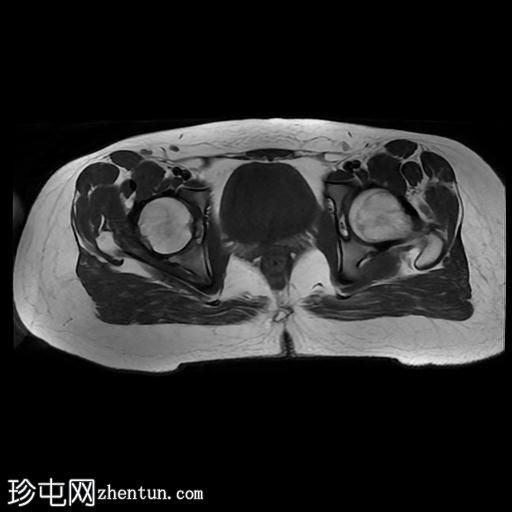

臀中肌近端撕裂

MRI

轴位

T2加权像

轴位T2加权像

脂肪抑制像

臀中肌髂骨起点处前侧全层撕裂,伴有充满液体的间隙,以及髂骨髓水肿。

MRI结果符合臀中肌近端髂骨起点处全层撕裂的

影像

学表现。